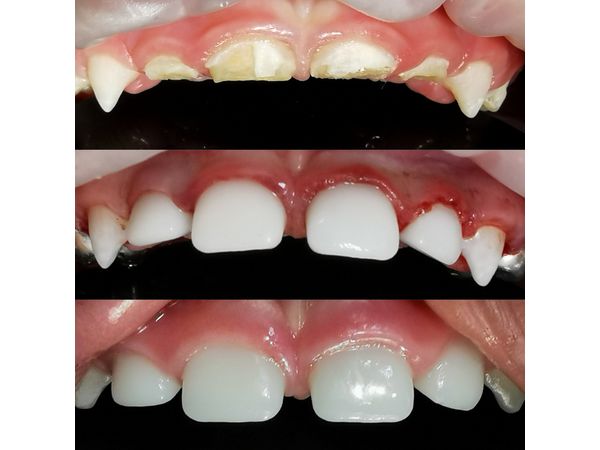

Во рту глубокие, обширные дефекты твёрдых тканей передних верхних зубов (зубы 5.2, 5.1, 6.1, 6.2): на них отсутствовала эмаль, коронковая часть центральных зубов была разрушена наполовину, боковых резцов — до уровня десны.

Ввиду высокой активности кариеса и большого объёма лечения, было принято решение проводить процедуру под глубокой седацией. В итоге девочке:

- удалили некротически изменённые твёрдые ткани передних четырёх зубов;

- механически и медикаментозно обработали, высушили и запломбировали каналы;

- восстановили зубы с помощью стандартных циркониевых коронок.

Через неделю после лечения родители ребёнка отметили, что боль при приёме пищи появлялась реже. Когда чистила зубы, дискомфорта не было.

Благодаря проведённому лечению девочка приобрела полноценную улыбку и избавилась от боли. Её родители были довольны результатом терапии. Девочке подобрали необходимые средства для ухода за полостью рта и рассказали маме с папой, какой техники чистки зубов необходимо придерживаться. Им также дали советы по питанию и дополнительным средствам гигиены рта с учётом возраста ребёнка.